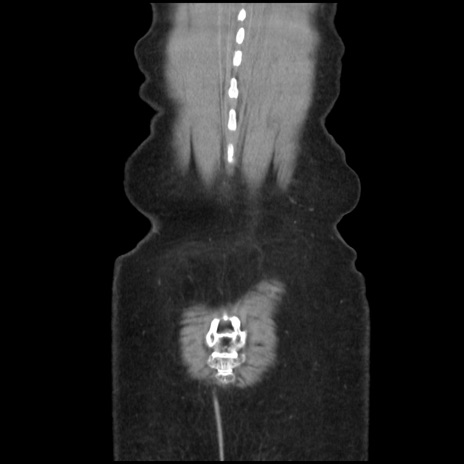

矢状断像